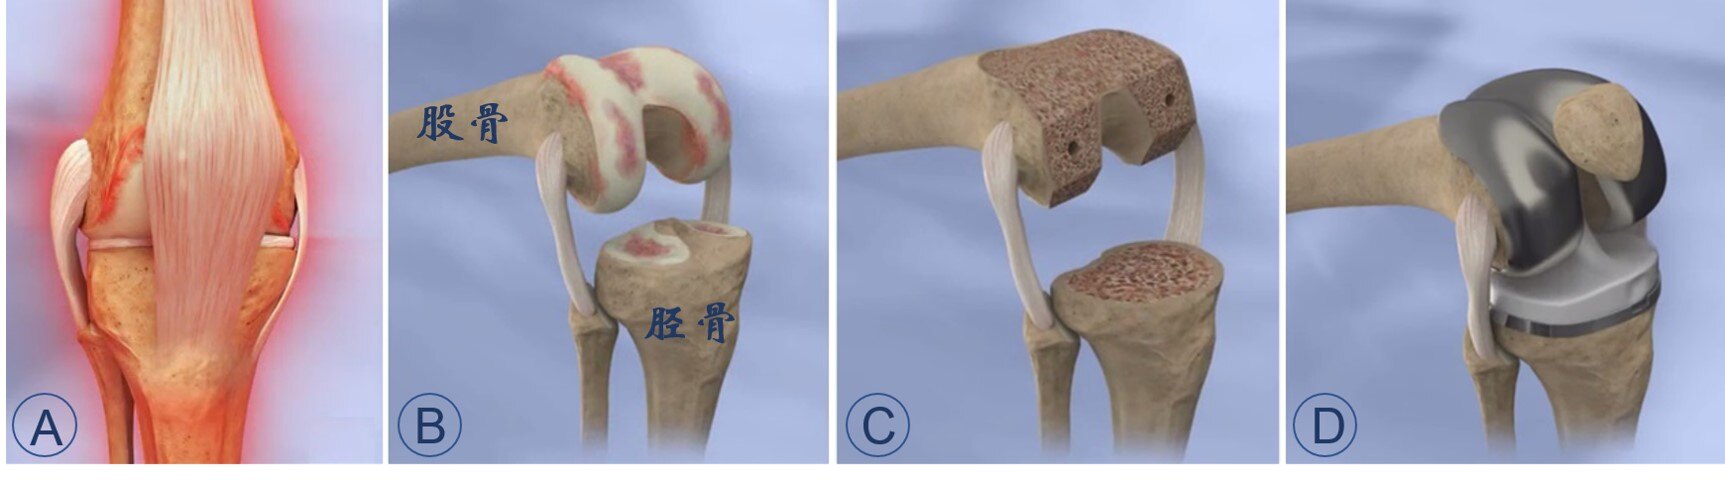

今天跟大家分享一下人工全膝表面置换(Total Knee Arthroplasty, TKA)。经过50余年的发展,人工全膝表面置换已经成为一项成熟的手术技术,采用耐磨的人工材料(金属/陶瓷和聚乙烯,图2)来替换磨损或破坏的关节表面(图3),从而缓解关节疼痛、恢复关节屈伸和负重行走活动,帮助病友们重新获得健康的生活。

图3. 人工膝关节置换手术简要操作。A. 病变的膝关节;B. 手术显露出损坏的股骨侧与胫骨侧表面;C. 切除损坏的股骨与胫骨表面;D. 安装股骨假体、胫骨假体以及髌骨假体。